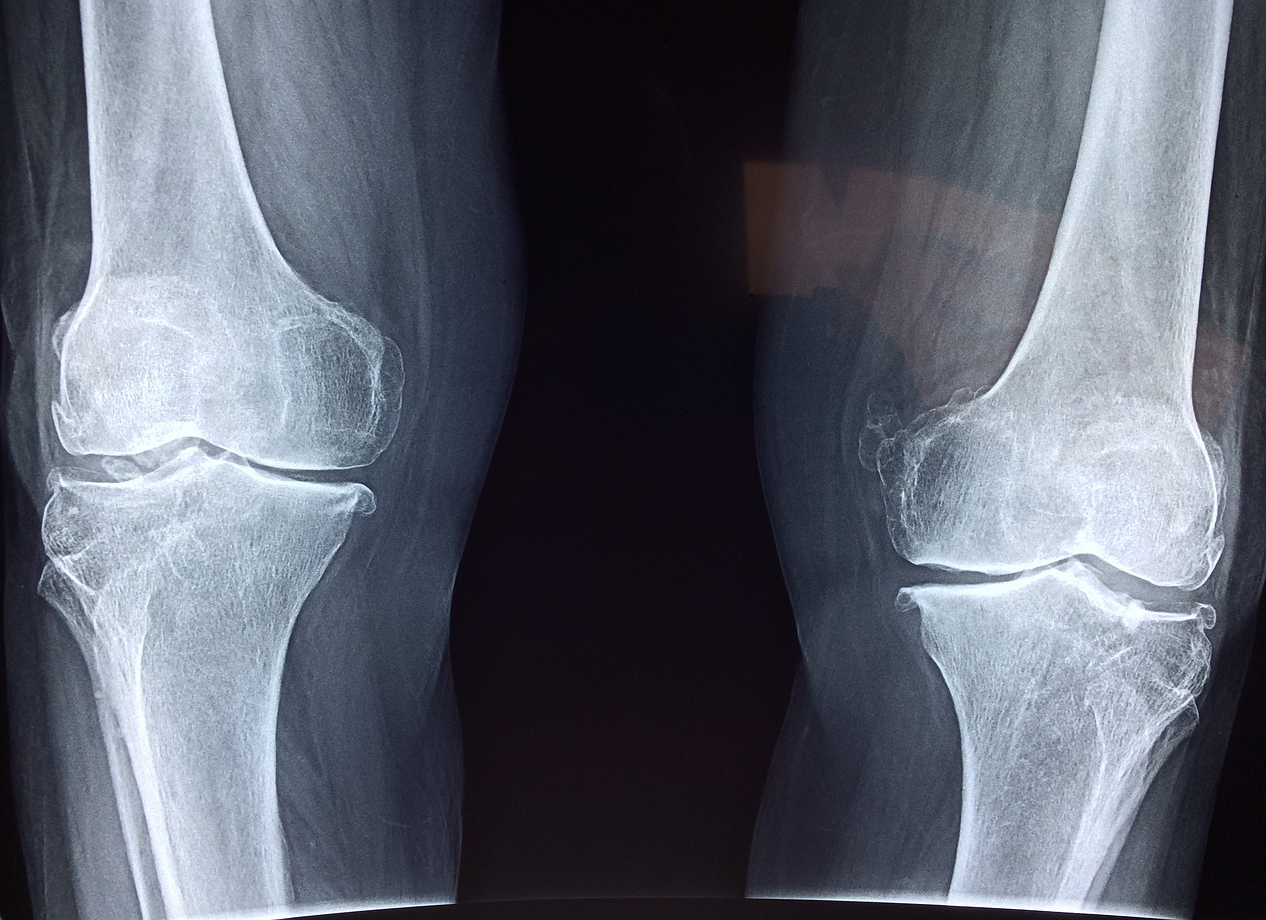

주로 엄지발가락 관절에 많이 발생하지만, 발목과 무릎, 손목 등 다른 관절에서도 발생할 수 있습니다.